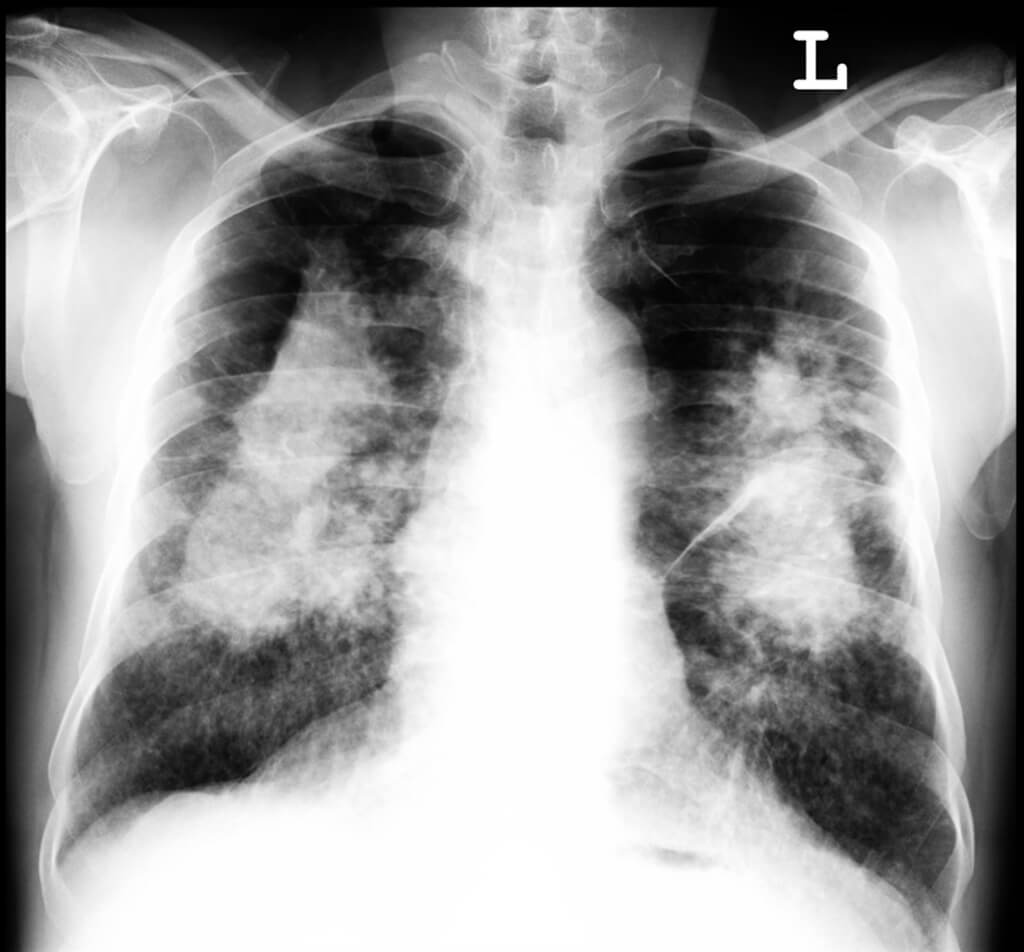

Silica Dust particles are incredibly fine. Because they are so small, the particles can be easily breathed deep into our lungs. From pins and needles in your hands (scleroderma), inflammation of the air-ways (chronic bronchitis), or the destruction of lung tissue (emphysema); to scarring of the lung (silicosis), Kidney Disease and Lung Cancer – the risks and consequences of Silica Dust exposure can be severe.